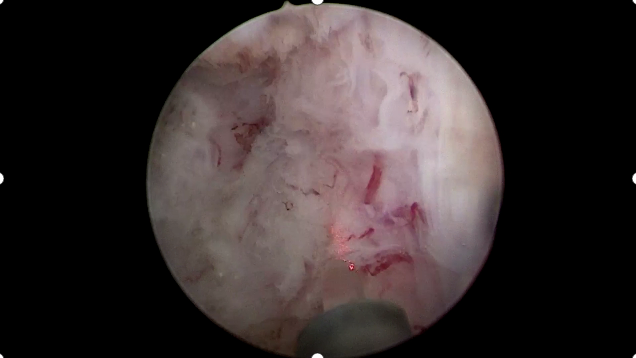

术中,李国成副主任医师通过细如笔芯的精囊镜,见患者射精管开口喷血,左侧精囊内结石,双侧精囊内黏膜有慢性炎症改变。最终,在精囊镜的导引下,精准定位结石,同步进行冲洗、取石和止血等操作,成功完成手术。

射精管出血

精囊内结石

炎症改变